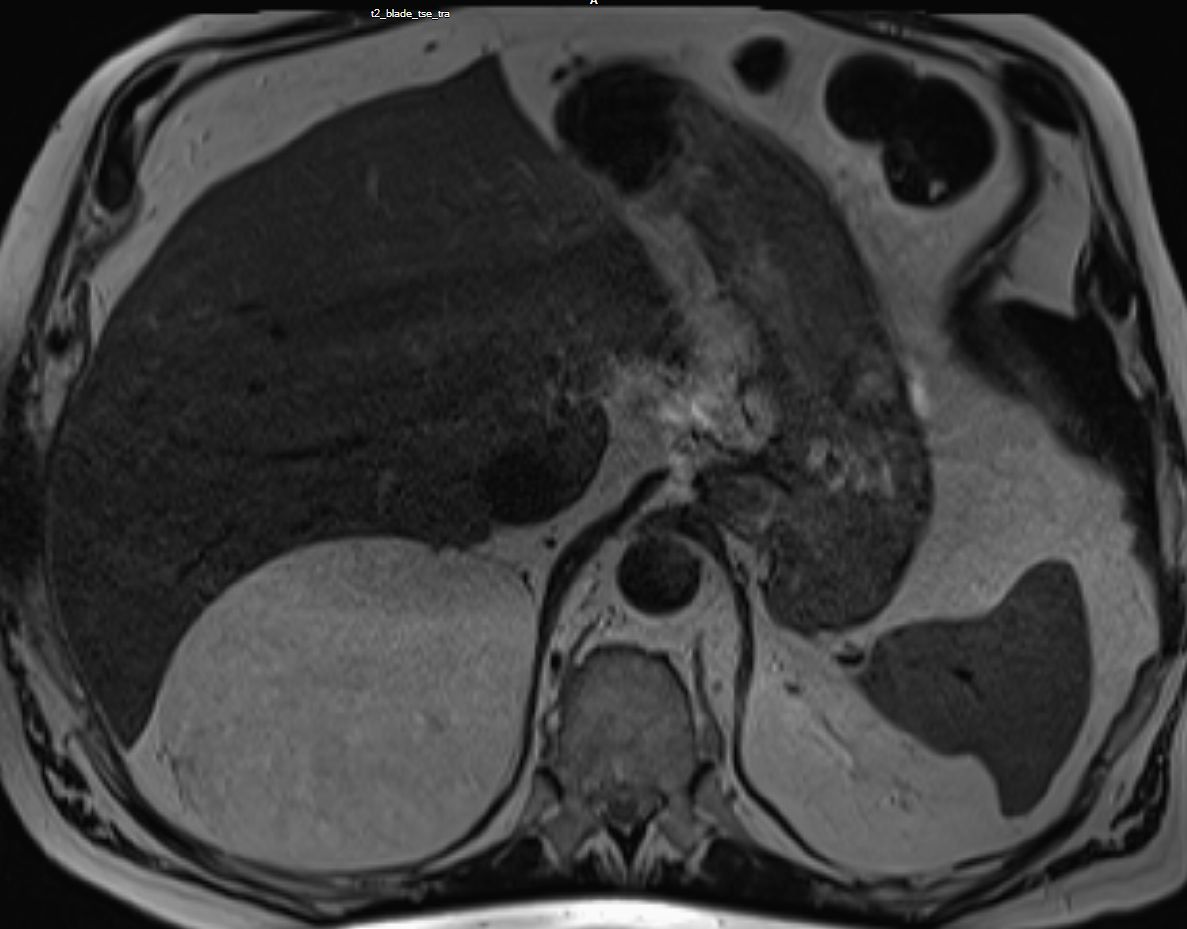

79-jähriger berenteter, adipöser Fleischer mit respiratorischer Insuffizienz. Urothel-Ca vor 15 Jahren. Jetzt kleines Bronchial-Karzinom. Beim Tumorstaging wurde ein großer NN-Tumor rechts entdeckt. | |||

![]() |